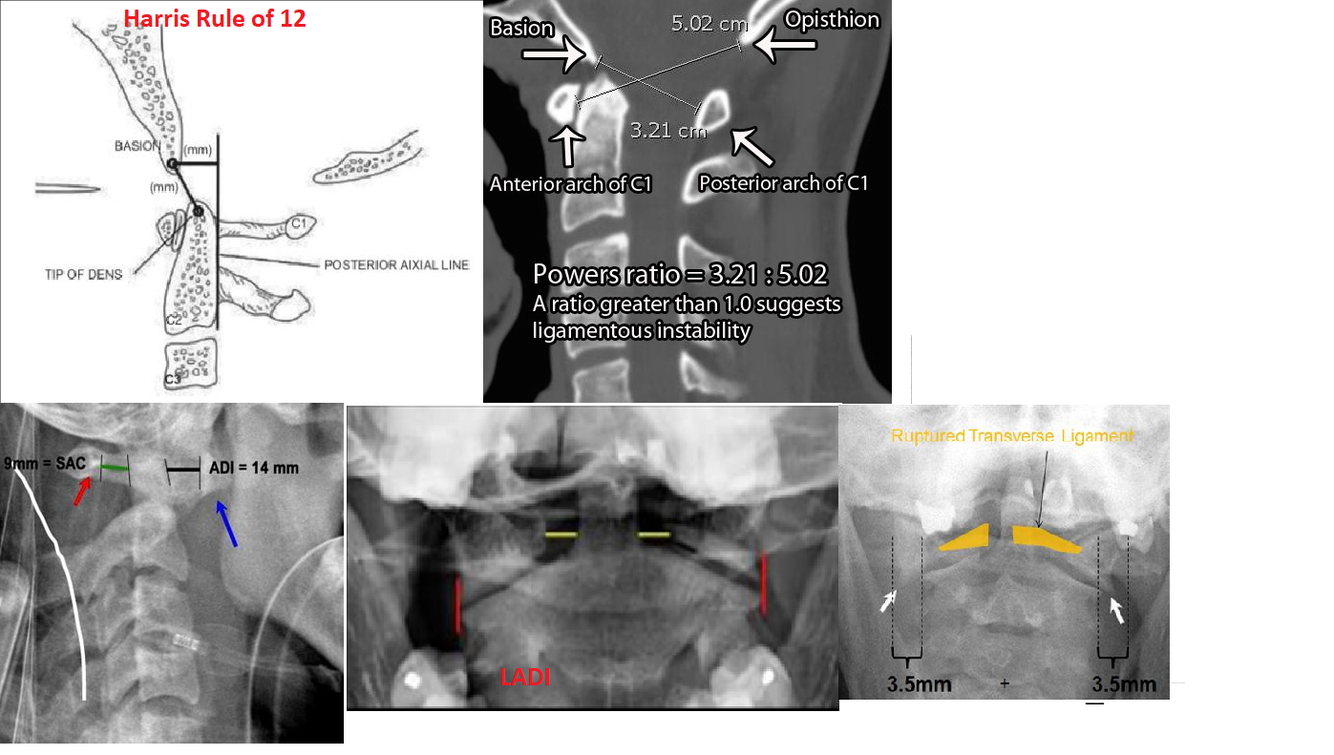

What are the radiographic parameters to be assessed on plain film for craniocervical dissociation?

What are the radiographic parameters to assess for atlas fractures?

What are the radiographic parameters to assess for atlantoaxial instability?